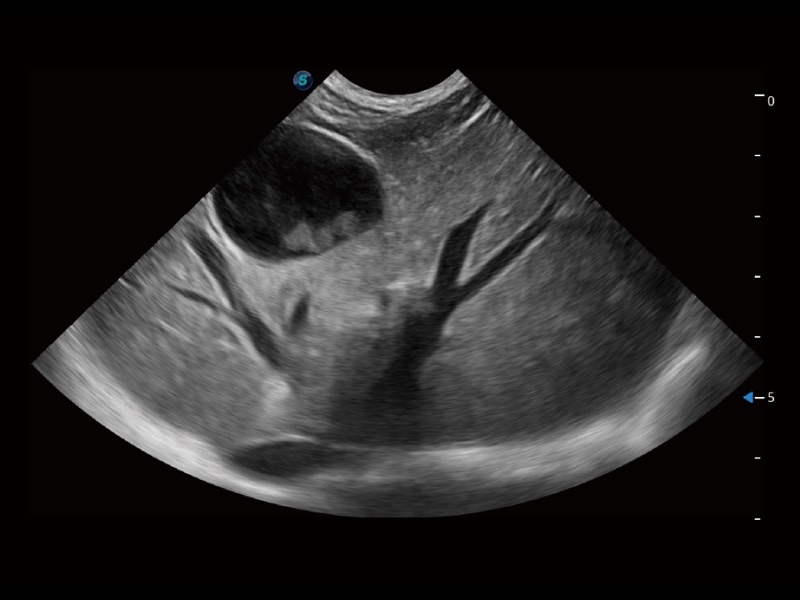

貓、中小型犬及小型異寵動物

ProPet 70 進一步提升了微米成像算法,更加注重對基礎(chǔ)原始圖像的還原和保留,在有效減少斑點噪聲、增強組織邊界顯示的同時,避免過度優(yōu)化丟失真實的解剖信息。

ProPet 70專為動物醫(yī)生設(shè)計,對不同的動物體型和生理結(jié)構(gòu)作出了針對性的優(yōu)化。通過動物影像專用軟件,可滿足個性化的應(yīng)用需求,幫助動物醫(yī)生獲得更精確的診斷數(shù)據(jù)。

ProPet 70 全新的動物超聲智能軟件和豐富的探頭群,為動物醫(yī)生提供了高清晰度和精細分辨率的圖像,無論在寵物、馬科、畜牧還是實驗室動物等應(yīng)用中都可以輕松應(yīng)對,為您的日常工作帶來滿意的體驗。